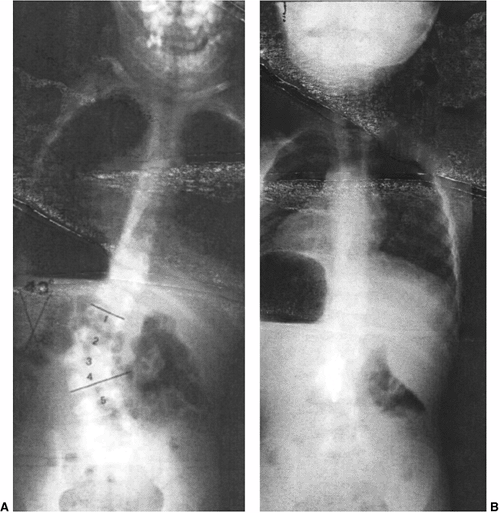

Figure 19.3 A:

Intraspinal anomalies accompanying vertebral anomalies are common. Indications for magnetic resonance imaging (MRI) include planned surgical intervention, abnormalities found on neurologic examination, and progressive curvature in the unaffected section of the spine. Diplomyelia is visible in this computed tomography (CT) myelogram. B: Diastematomyelia, diplomyelia, tethered spinal cord, and other anomalies are present in this infant with multiple vertebral anomalies. Surprisingly, the lower extremity neurologic exam is normal (MRI scan image). C: Tethered spinal cord with thickened filum terminale (MRI scan image). D: A CT scan with sagittal, coronal, or three-dimensional reformatting is helpful for understanding details of congenital vertebral anomalies. Two lumbar hemivertebrae are readily visible here. |